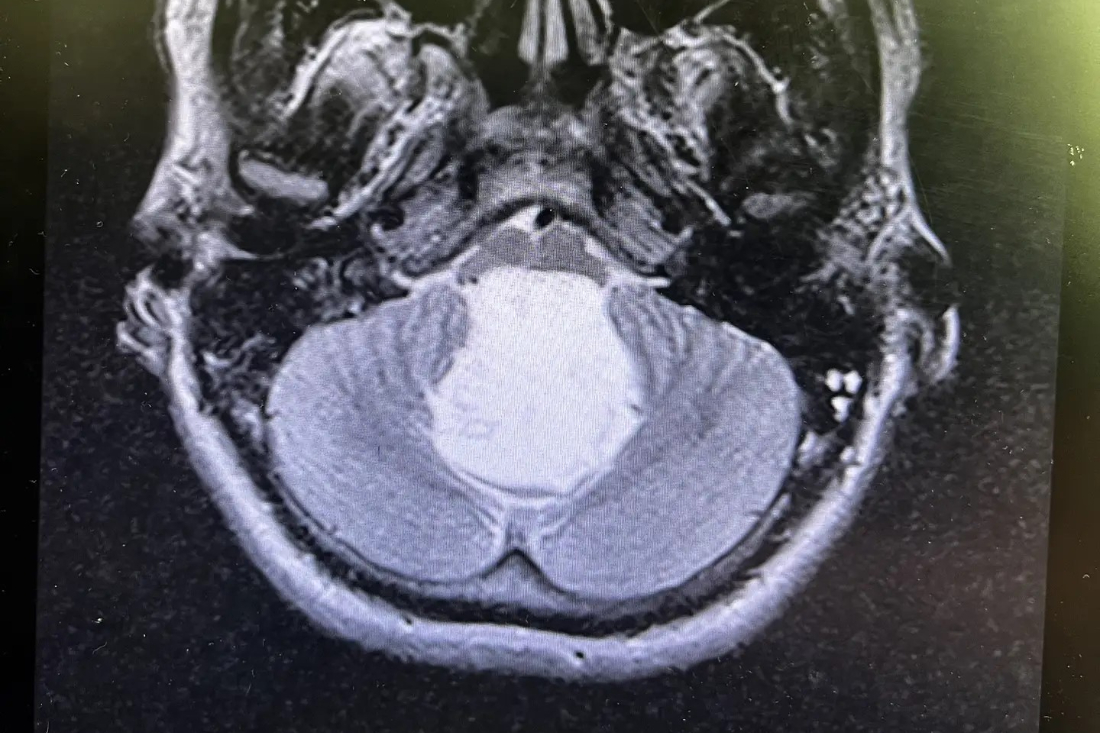

Молодой сибиряк к тому моменту с трудом мог ходить. А врачи, увидев снимки МРТ, не поверили, что перед ними живой человек — опухоль в его голове вплотную прилегла к дыхательному центру в мозге. Он могу умереть в любую секунду. Да и новообразование было весьма редкое — огромная перламутровая киста, которую выявляют у 3-9 человек на каждые 100 тысяч населения в год.

— За двадцать лет это третий пациент с холестеатомой в моей практике. И первый с новообразованием такого огромного размера — 6 на 4,5 сантиметра. Когда мы вошли в зону вмешательства, убедились своими глазами в том, что ствол мозга передавлен опухолью, то есть жизнь пациента ежесекундно под угрозой. Останься он дома ещё на сутки, и было бы поздно. Как потом показали результаты гистологии, у пациента врождённое доброкачественное новообразование, которому столько же лет, сколько молодому человеку, — сказал нейрохирург облбольницы Шалиндер Аул.